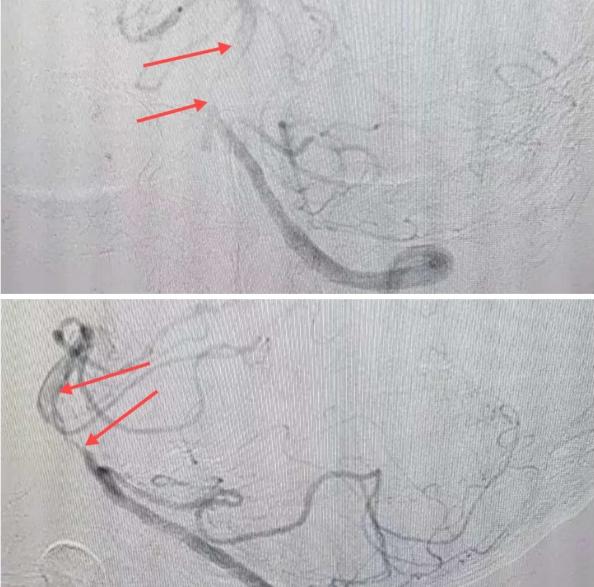

在經(jīng)造影后,主刀醫(yī)生腦一科副主任楊慶堂發(fā)現(xiàn)患者基底動脈下段重度狹窄且狹窄段以遠(yuǎn)有大負(fù)荷血栓,其狹窄處考慮為動脈夾層,手術(shù)難度及風(fēng)險較大。楊慶堂副主任在彭壯副主任醫(yī)師的協(xié)助下運用spaceman(太空人)技術(shù),中間導(dǎo)管抵近血栓抽吸配合支架拉栓,成功開通血管。再次造影可見基底動脈管腔明顯增寬,遠(yuǎn)端血管顯影良好,且等待20分鐘后造影仍顯示血流通暢。楊慶堂副主任考慮到本次手術(shù)時間不宜過長,現(xiàn)患者基底動脈及分支前向血流維持良好,給予其抗栓藥物應(yīng)用后結(jié)束手術(shù),并建議患者3個月后復(fù)查造影,明確其基底動脈夾層情況。

造影可見血管夾層和大量血栓形成

取栓后血管管腔增寬,前向血流良好